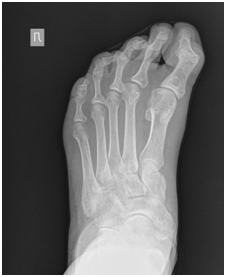

На момент госпитализации пациентку беспокоил болевой синдром при ношении любой обуви, а также неэстетический внешний вид левой стопы. Из анамнеза, пациентка считает себя больной с юности, когда впервые обратила внимание на отклонение I пальца кнутри. Со временем, II и III палец вслед за I начали отклоняться внутрь, а затем все три пальца приобрели молоткообразную установку, IV палец принял когтеобразную форму. У пациентки не было отмечено травм и заболеваний, которые могли спровоцировать развитие данной деформации (рис.1).

Клинически было отмечено, что деформация I и IV пальцев была фиксированная и не устранялась при попытке разогнуть эти пальцы в межфаланговом суставе, имелись болезненные омозолелости на контактной поверхности пальцев. Деформация II и III пальца была мобильной. Эластичность стопы соответствовала 2 типу (рис.1, рис.2).

Рис. 2. Рентгенограмма левой стопы до операции (прямая проекция)

Fig. 2. Radiograph of the leftt foot before surgery (AP radiograph)